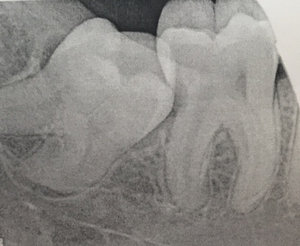

Мне 23 года. 4 дня назад у меня опухла десна, ночью припухлость прошла, но на следующий день десна опять опухла, но уже без боли. Многие из врачей говорили, что это абсцесс, на снимке ничего не понятно. Врач сказал, что это зуб мудрости, который лезет перпендикулярно последнему зубу.

Исправить это можно только удалением зуба. Если все так, как Вы описали, то, к сожалению, в надкостнице имеется воспаление, отсюда отечность. К сожалению, зуб необходимо удалить и как можно раньше.

Обратитесь к опытному хирургу, так как удаление данного зуба сложное, и некачественное удаление может привести к печальным последствиям.